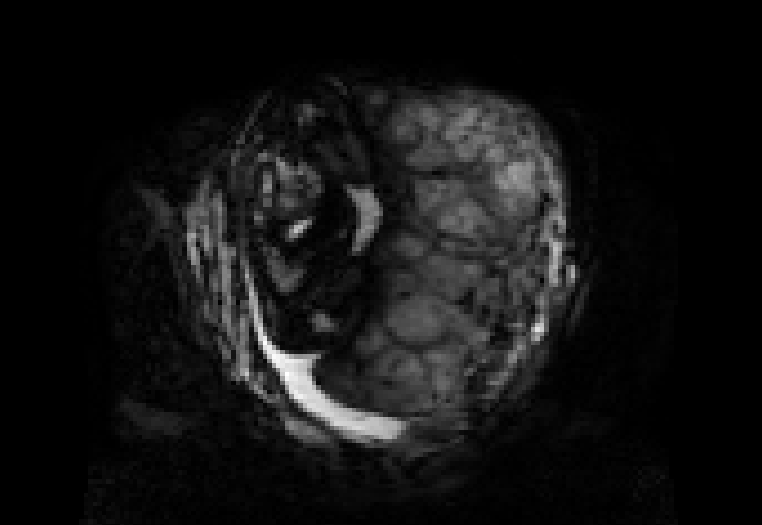

This atlas and the linked publication [1] aim to give a visual overview over T2-weighted anatomical imaging and T2* relaxometry placental data. Both have been widely used in the last years to assess placental structure and function in-vivo [2-10].

Data from healthy controls is displayed over GA, different acquisition choices and possible dynamic effects are depicted and placentae from different cohorts affected by complications are shown.

Display description: All placentae are shown in maternal coronal plane (See A). The slice with the largest placental volume was chosen. The same colormap was chosen for all placentae (See B).